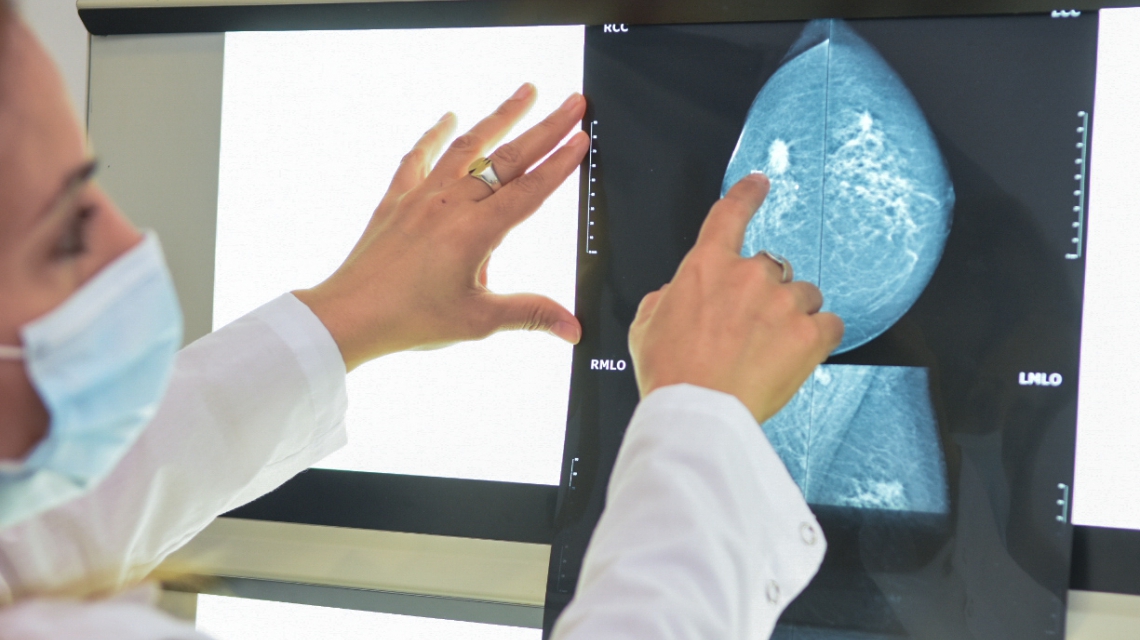

La mamografía es una radiografía de baja dosis, que puede encontrar cambios que son demasiado pequeños para sentirlos durante un examen físico. Es el mejor método de screening probado, por su eficacia para detectar tempranamente el cáncer de mama.

La ecografía mamaria es un examen complementario a la mamografía. Especialmente útil en la evaluación de los ganglios axilares y es de gran ayuda para estudiar pacientes con mamas muy densas, en que la mamografía es menos sensible para detectar cáncer.